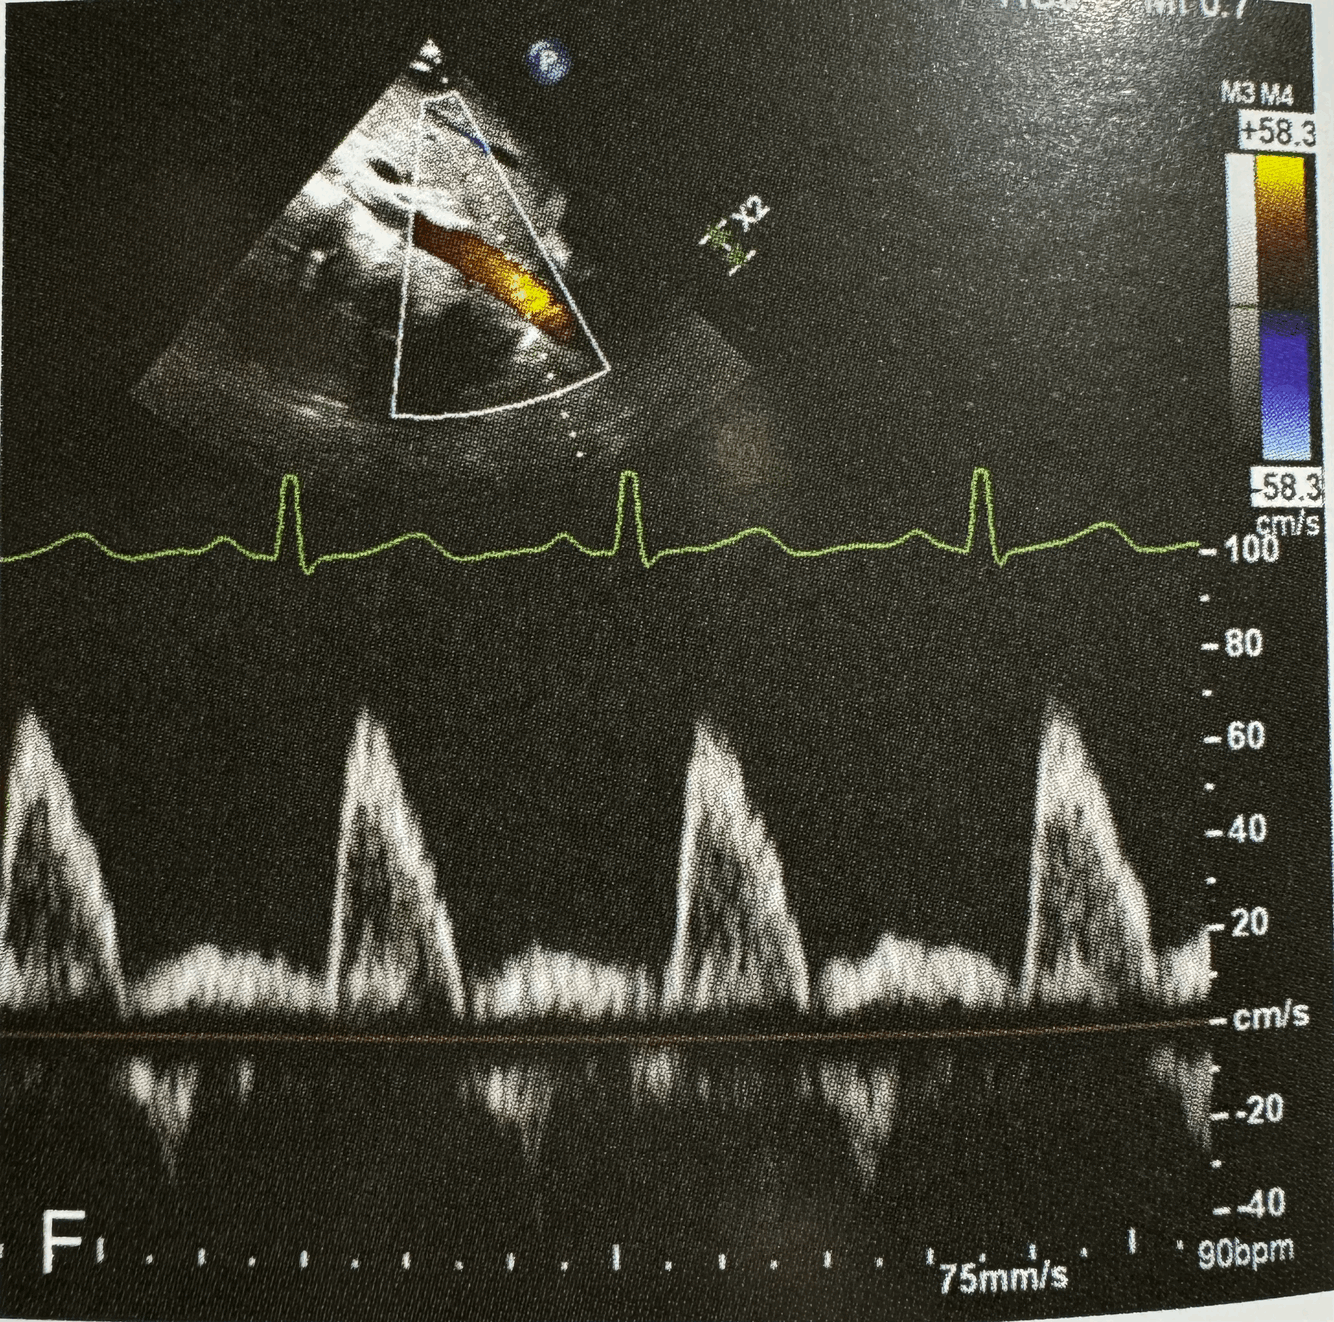

What normal flow pattern is this and in what view?

A